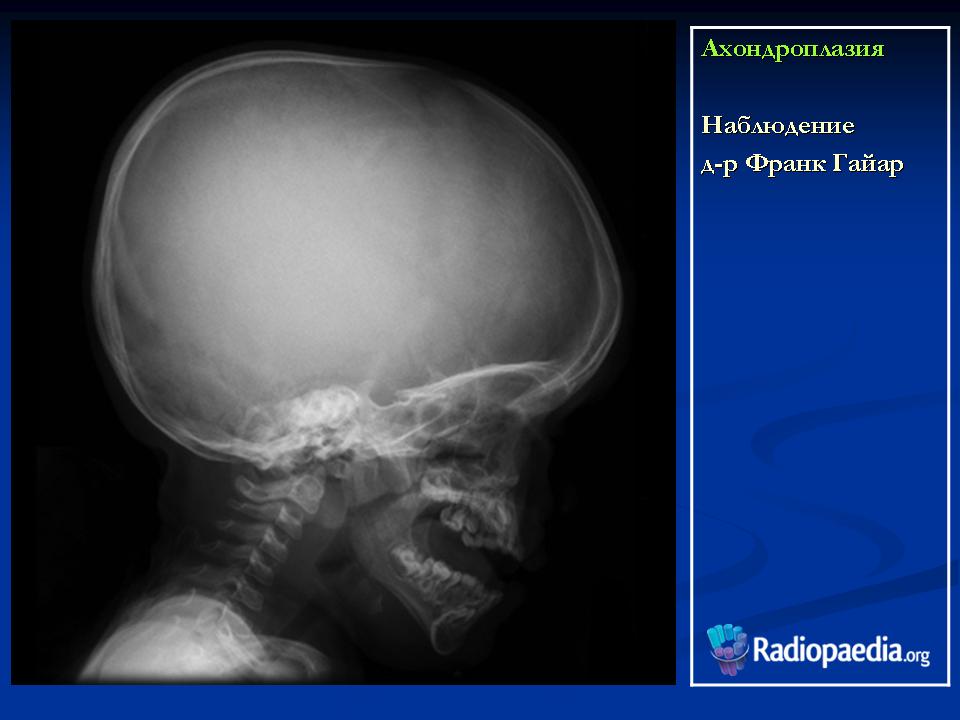

Наблюдение д-ра Франк Гайар

Характерными признаками гетерозиготной ахондроплазии являются укорочение конечностей, поясничный лордоз, короткие пальцы, макроцефалия с выступающим лбом и запавшей переносицей. Трубчатые кости, как правило, сохраняют правильную форму. Их деформация встречается не более чем в 25-30% наблюдений. Грудная клетка и живот не отстают от нормативных для срока значений.